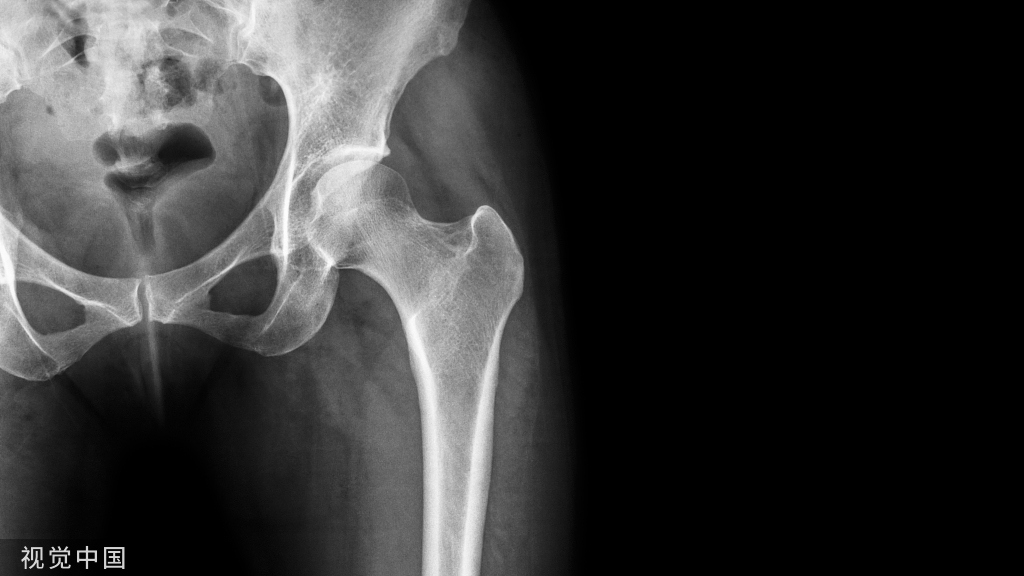

但”铁环“理念在骨科不是始终错误的,骨盆骨折时就很符合这种理念,骨盆结构也是一个环状结构,故有骨盆环的说法,虽然骨盆环也存在关节及韧带连接,但骨盆组成骨质相互之间凸凹有致,类似于榫卯而紧密连接,周围有韧带加强,最后形成一个不易变形的环状结构,也就形成了”铁环“。

故骨盆环损伤时可以完全按照铁环理论来处理,也就是说一处损伤对稳定无影响,可以不作固定,如一侧耻坐骨支骨折时完全可以不处理,担当骨盆环存在两处及以上损伤时骨盆环稳定性受到影响,必须作固定,固定时也可以保留一处不做处理,比如双侧耻坐骨支骨折时不稳定性骨折,必须进行固定,如果固定时固定了一侧而另一侧不作固定也是符合要求的。当然必须强调,骨盆环不是均质的环,而是后部几何尺寸比较粗大,故骨盆后环的刚度较大,是骨盆环的主要的稳定部位,而前环几何尺寸较细小,时次要的稳定部位,换一句话骨盆稳定主要靠后环。